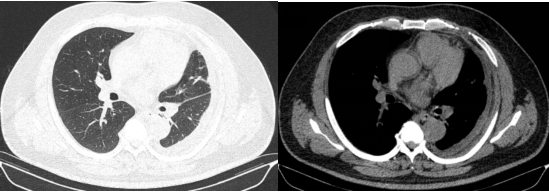

入院时CT显示:左侧胸腔被积液填满,如同一个巨大的"脓袋"压迫着正常肺组织。

棘手的是,传统穿刺引流如同"抽丝剥茧",抽出近2000ml腥臭脓液后,复查CT仍见残留大量纤维分隔包裹,配合强力抗生素治疗,患者仍然持续高烧不退。

历经4小时鏖战,手术团队成功拆除"定时炸弹"。术后第二天,患者体温即开始逐渐下降,后续继续全身应用抗生素、胸腔灌注药物、控制血糖、营养支持等综合治疗,患者病情迅速好转,复查肺CT恢复良好,患者对治疗效果表示满意。